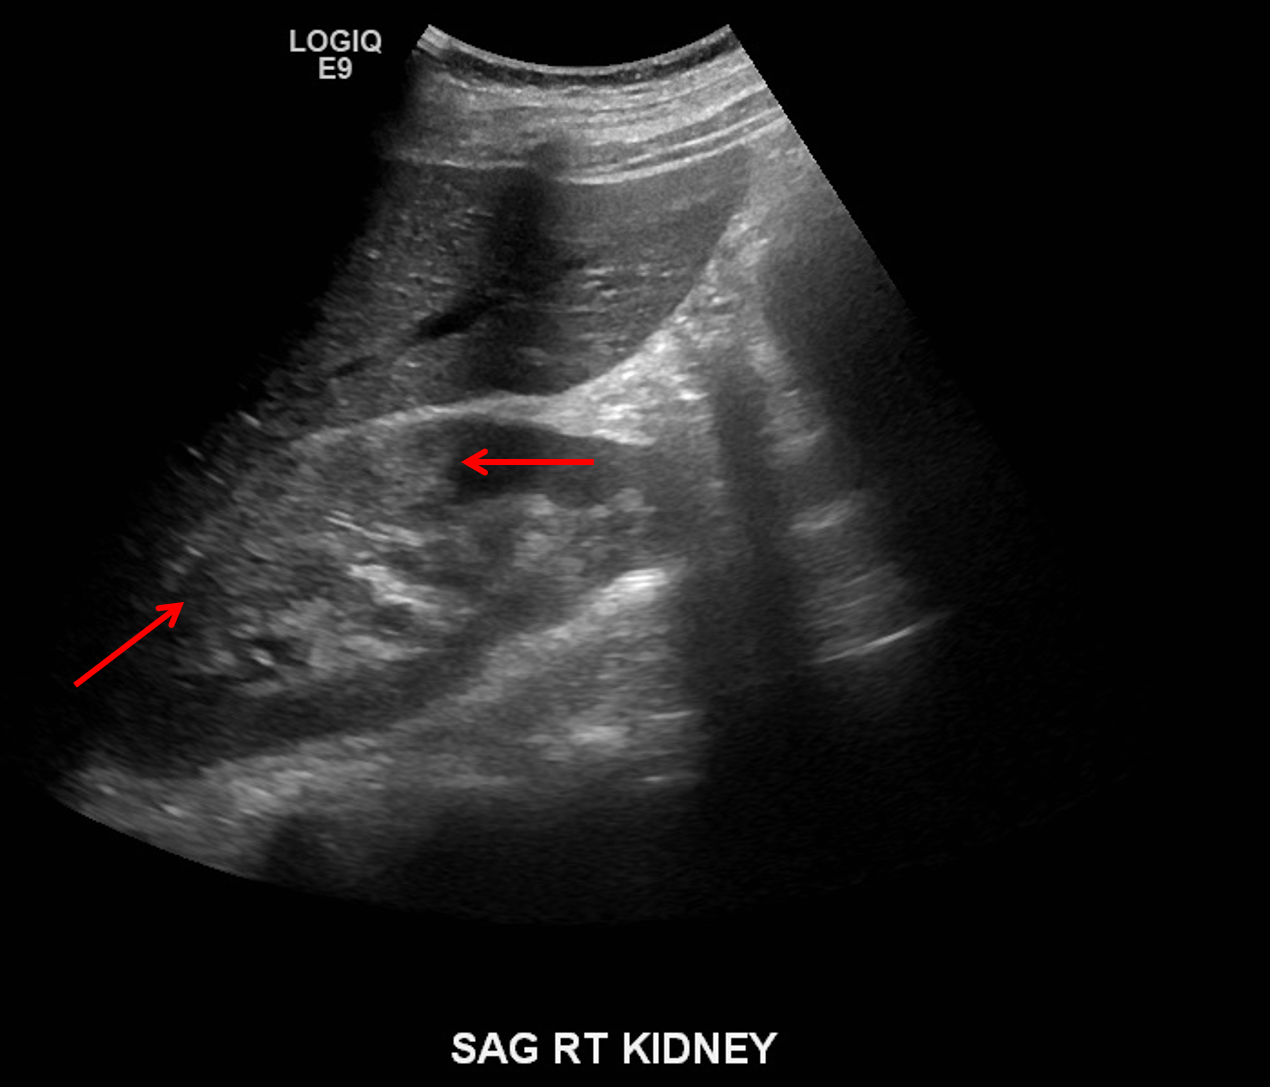

Age: 25

Sex: Female

Indication: Right flank pain, pregnant patient

Pyelonephritis

Sample ReportMultifocal areas of parenchymal hyperechogenicity and decreased corticomedullary differentiation involving the right kidney, concerning for pyelonephritis. No evidence of renal or perinephric abscess. Mild right hydronephrosis. No urinary tract calculi identified.